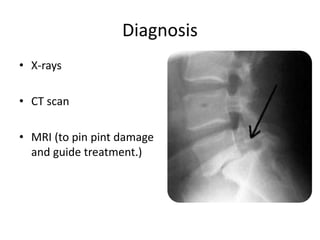

Diagnosis

• X-rays

• CT scan

• MRI (to pin pint damage

and guide treatment.)